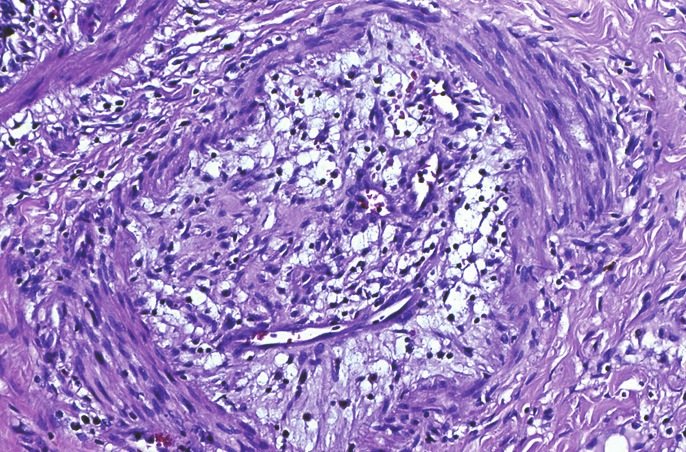

En la hipertensión pulmonar asociada a trastornos cardíacos o pulmonares las características patológicas típicas asociadas a la enfermedad estarán presentes en la patogenia de estas condiciones o de la enfermedad de base. Sin embargo, es distinta de la patogenia de la hipertensión pulmonar primaria. Lo que se sabe, es que hay vasoconstricción inicial y luego migración de fibras musculares lisas desde la mitad interna de la capa muscular media de las arteriolas pulmonares hacia el lumen vascular. Estas células se transforman en miofibroblastos capaces de depositarse como fibras musculares lisas o tejido fibroso. Una vez en el lumen, las células proliferan en forma concéntrica y finalmente obliteran el lumen. A medida que este proceso se desarrolla, el radio del lumen se cierra y la resistencia al flujo aumenta. Cuando se secciona y se examina bajo microscopio los vasos tienen una apariencia característica, la que habitualmente se le ha denominado proliferación en capas de cebolla. En los puntos proximales de debilidad del vaso sanguíneo, lo que usualmente ocurre en las axilas de las ramificaciones, los vasos se distienden, se rompen y se produce hemorragia. Vasos de neoformación crecen en el área hemorrágica en una forma desorganizada y plexiforme. La combinación de proliferación concéntrica en capas de cebolla asociada al crecimiento vascular plexiforme, se conoce como arteriopatía plexiforme pulmonar 5 (Figura 1).

Figura 1 Microfotografía que muestra una rama de pequeño calibre de la arteria pulmonar con oclusión del lumen, fibrosis laxa y vasos sanguíneos de neoformación. Aumento 200x, hematoxilina y eosina. Cortesía del Dr. Sergio González B. Departamento de Anatomía Patológica, Facultad de Medicina UC.